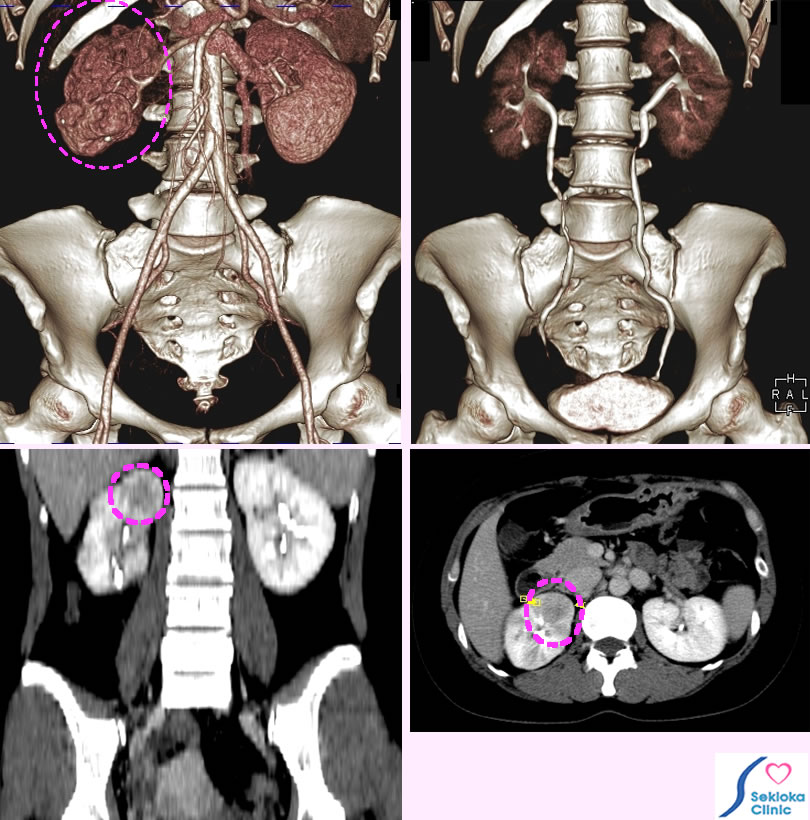

診断

尿検査、造影CT。超音波エコーは基礎病変の検索には有用だが腎盂炎の確定診断はできない。上段左側の造影MDCT(3次元)画像では 右の腎臓(破線楕円で囲む)は辺縁がいびつである。腎盂炎の再発が疑われる。下段の造影された腎臓の断面 (左:前後方向、右:体軸方向)では白く造影されない、血流の低下した部分(破線楕円で示す)が存在し、腎盂炎を示唆する。